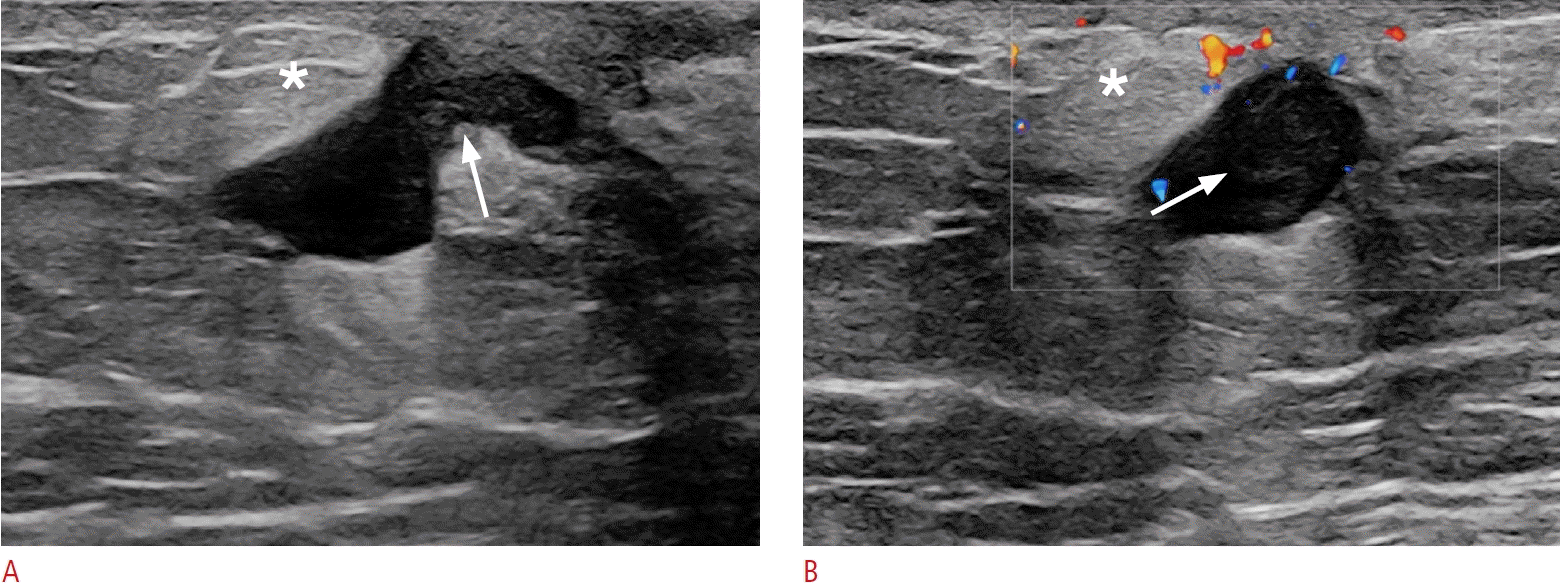

32. Okuno T, Watanabe T, Yamaguchi T, Konno S, Takaki R, Watanabe R, et al. Usefulness of color Doppler and strain elastography adjunctive to B-mode ultrasonography in the diagnosis of nonmass abnormalities of the breast: results of the BC-07 multicenter study of 385 cases. J Med Ultrason (2001). 2025; 52:157–168.

7. Kim WH, Chang JM, Moon WK, Cho N, Yi A, Koo HR, et al. Intraductal mass on breast ultrasound: final outcomes and predictors of malignancy. AJR Am J Roentgenol. 2013; 200:932–937.

27. Yoon JH, Yoon H, Kim EK, Moon HJ, Park YV, Kim MJ. Ultrasonographic evaluation of women with pathologic nipple discharge. Ultrasonography. 2017; 36:310–320.